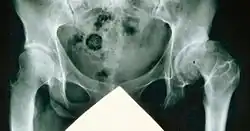

Coxa valga

Coxa valga des rechten, alte Epiphysenlösung des linken Femurkopfs

Coxa valga bezeichnet den relativ steilen Stand des oberen Endes vom Oberschenkelknochen. Der Collum-Diaphysen-Winkel beträgt mehr als 140°. Sie ist das Gegenstück zur Coxa vara, bei der der CCD-Winkel bei Erwachsenen unter 126° liegt.